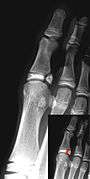

| Salter–Harris fracture radiographs with insets showing fracture lines. | ||||||||